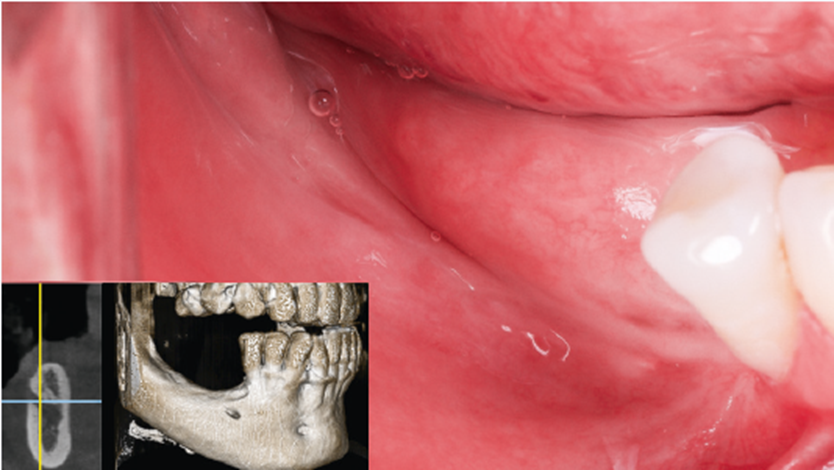

Paciente masculino, 52 anos, compareceu à clínicacom queixa de ausência dentária inferior posterior bilaterale desejo de reabilitação com implantes dentários. Ao exameclínico, verificou-se uma mucosa alveolar fina e a ausênciade gengiva queratinizada nas regiões edêntulas. A tomografiacomputadorizada de feixe cônico (TCFC) evidenciou a reabsorçãoóssea severa, comprometendo a instalação direta dos implantesdentários (Figura 1).

Figura 1 – Aspecto inicial e exame tomográfico inicial.